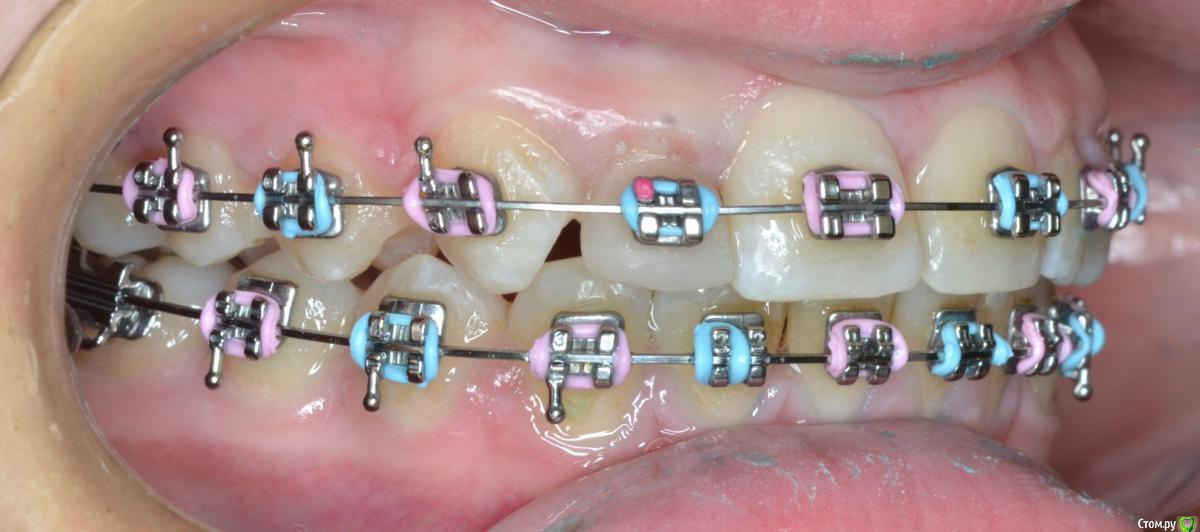

CRAZYDUCK Опубликовано 20 мая, 2018 Автор Поделиться Опубликовано 20 мая, 2018 Шиповидный боковой резец 1.2 . Изначально был дефицит места . Место создали -зуб восстановили ( реставрация временная - на время ортодонтического лечения , после полноценная реставрация). 1 Ссылка на комментарий